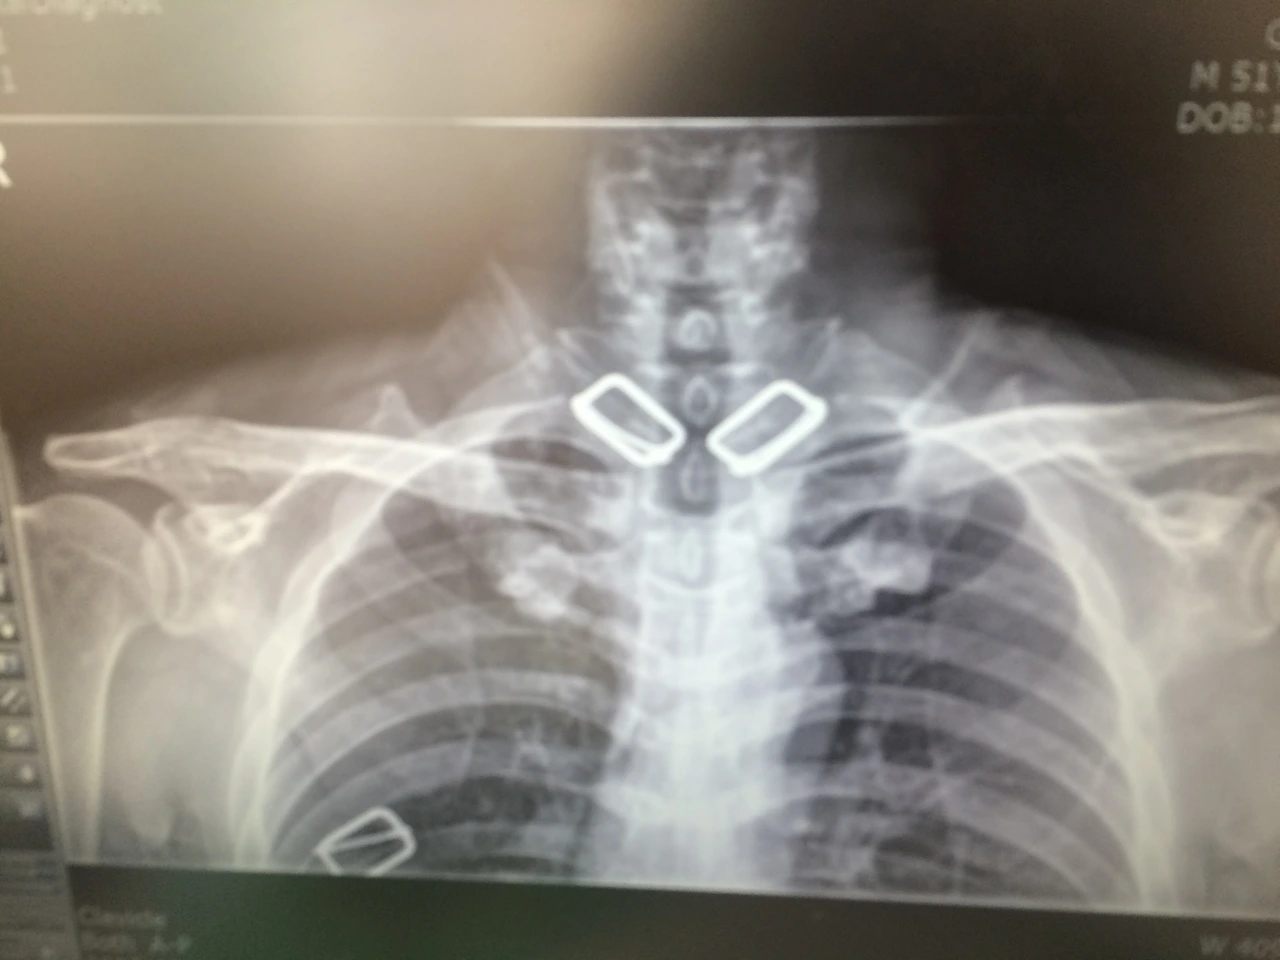

#10월 14일 추가

IMG_8623.JPG

IMG_8624.JPG

역시 별 이상이 없다. 의사는 "붙어가고 있는 중"이라고 말했다. 2주 후 집 가까운 병원에서 재활치료를 받아보라고 한다. 그리고 한 달 후에 다시 오라고 했다.